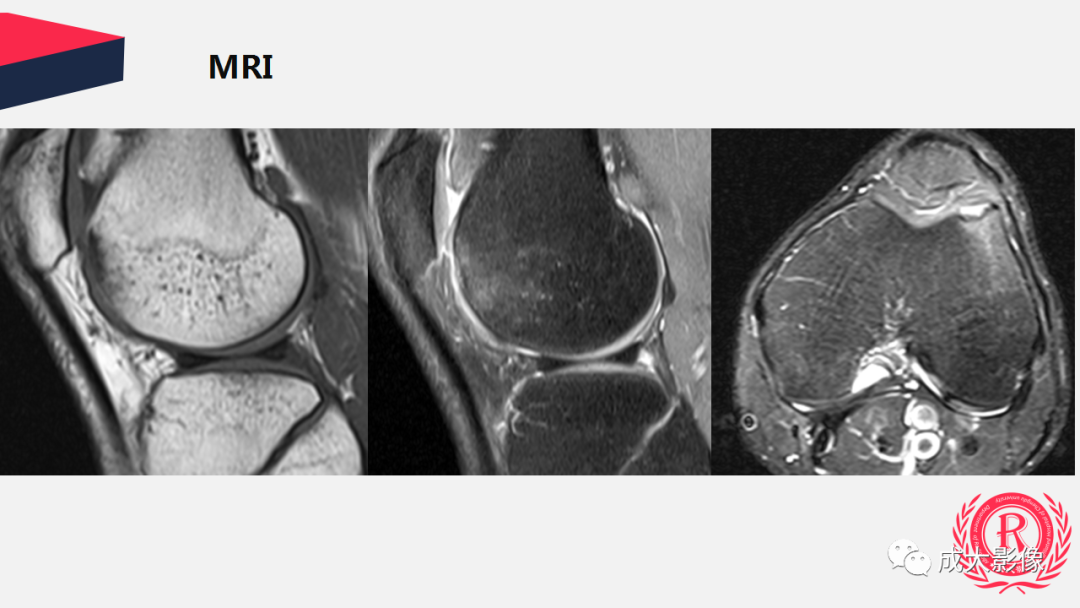

【PPT】剥脱性骨软骨炎

病例: